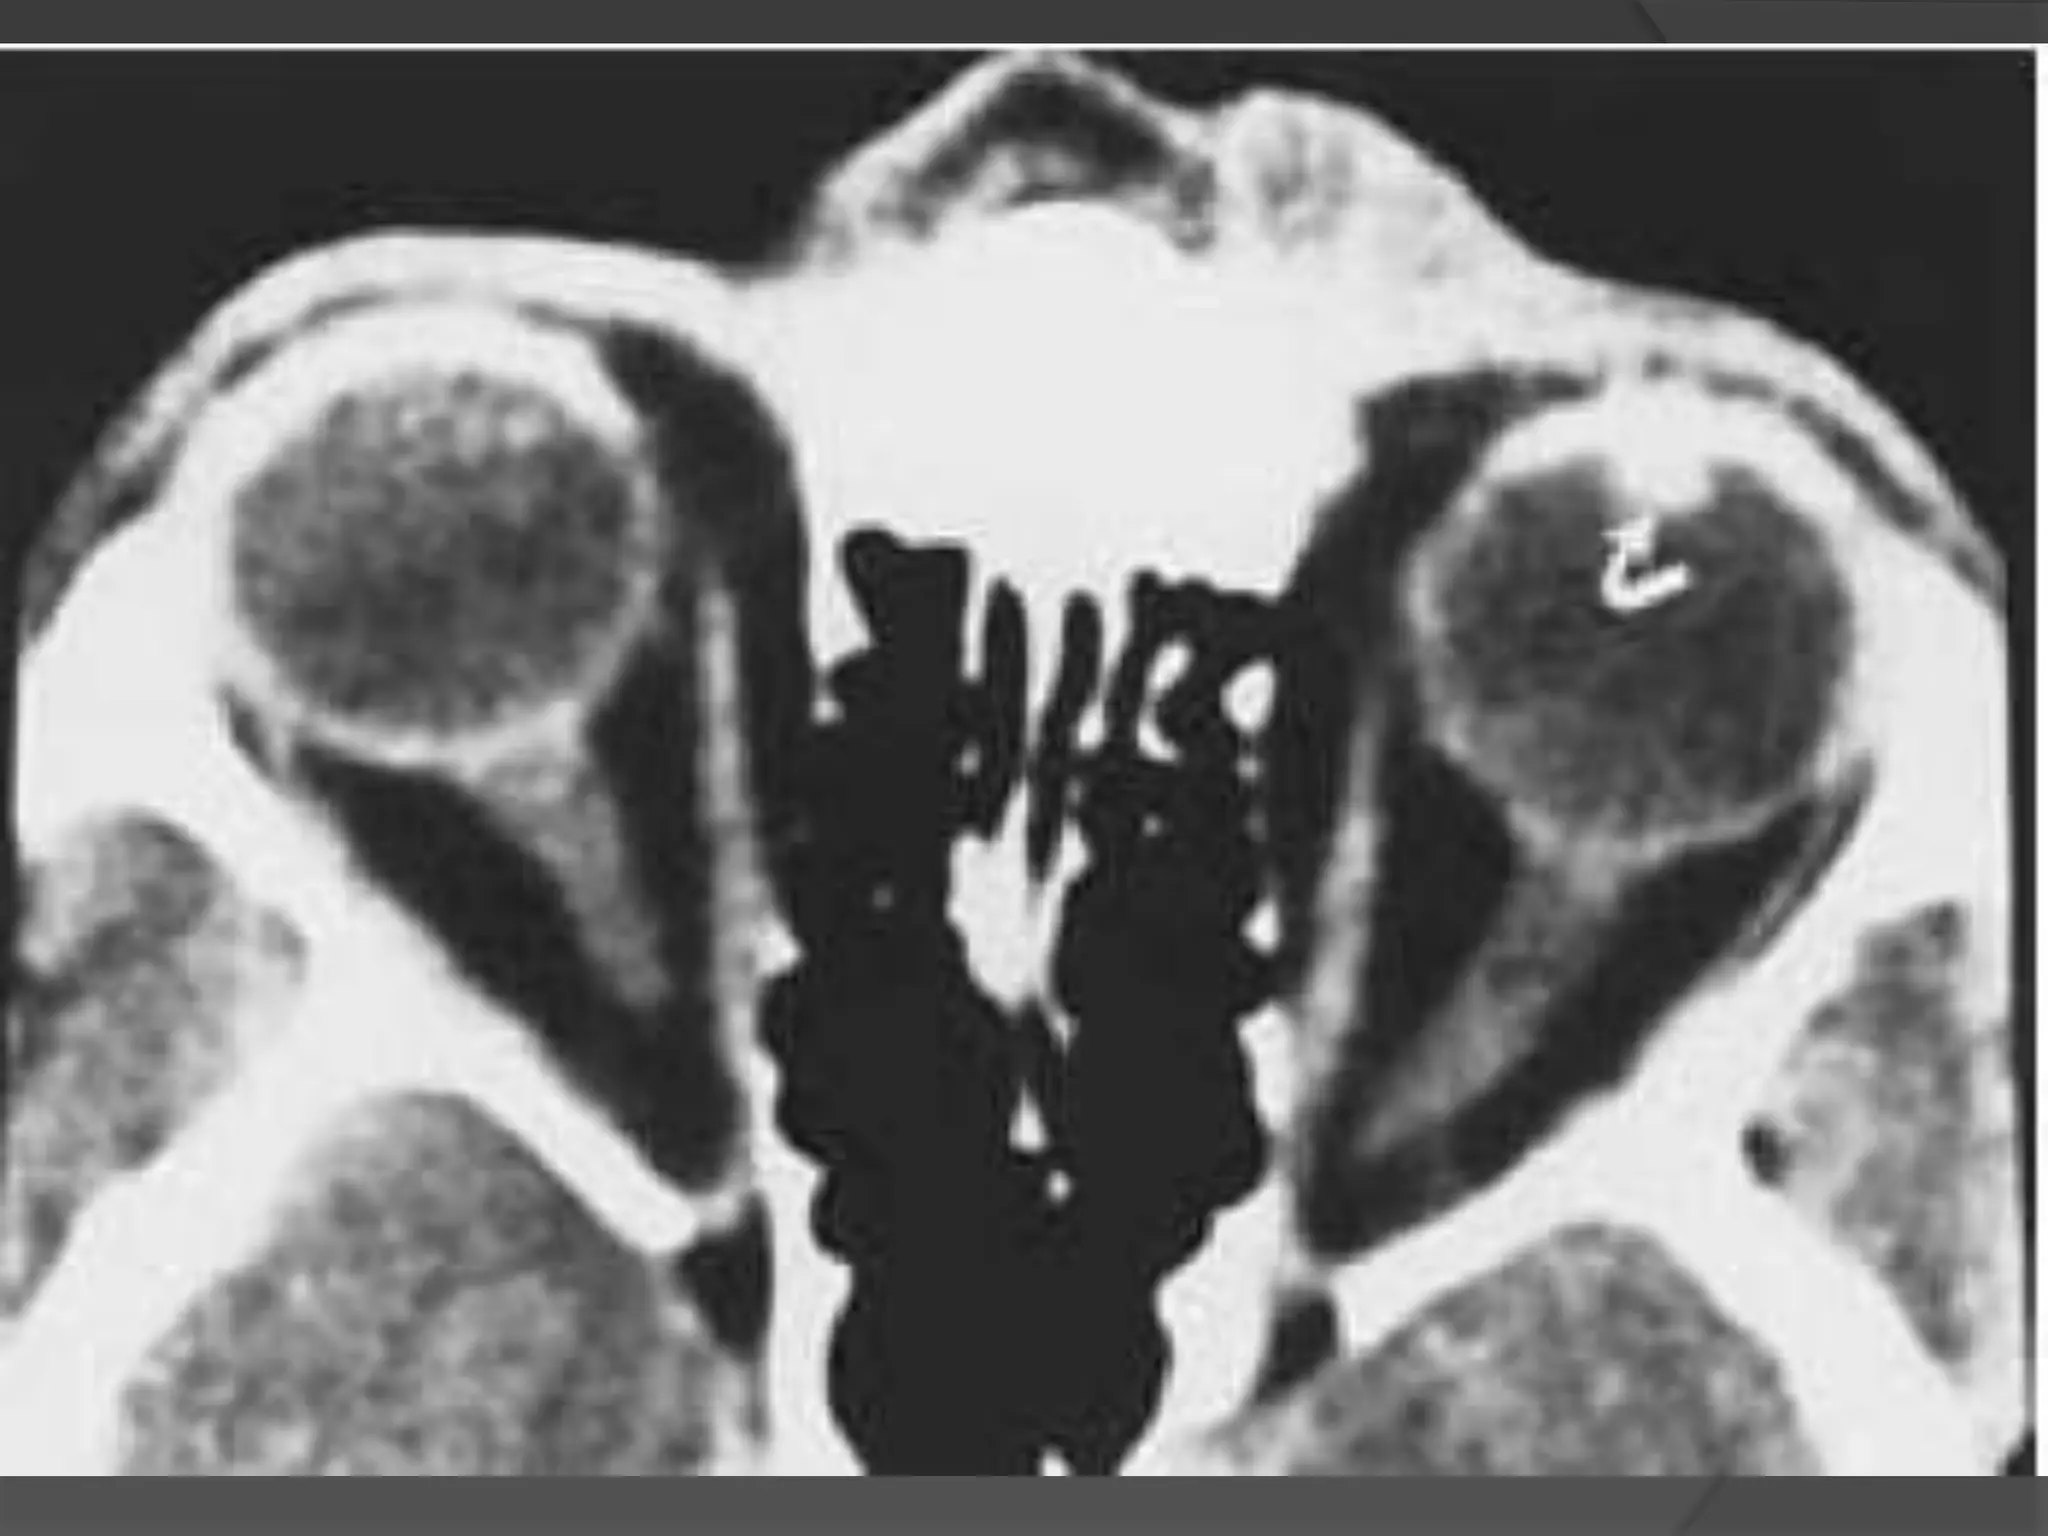

• #33 Coats’ disease. A, Axial CT scan shows generalized increased density of the left globe caused by bullous retinal detachment. The leaves of the detached retina are faintly seen, as shown by the arrows. B, Axial PW MR image shows hyperintensity of the left globe caused by subretinal lipoproteinaceous effusion. Note the leaves of the detached retina (arrows). C, Axial T2-weighted MR image shows the detached retina (arrows).